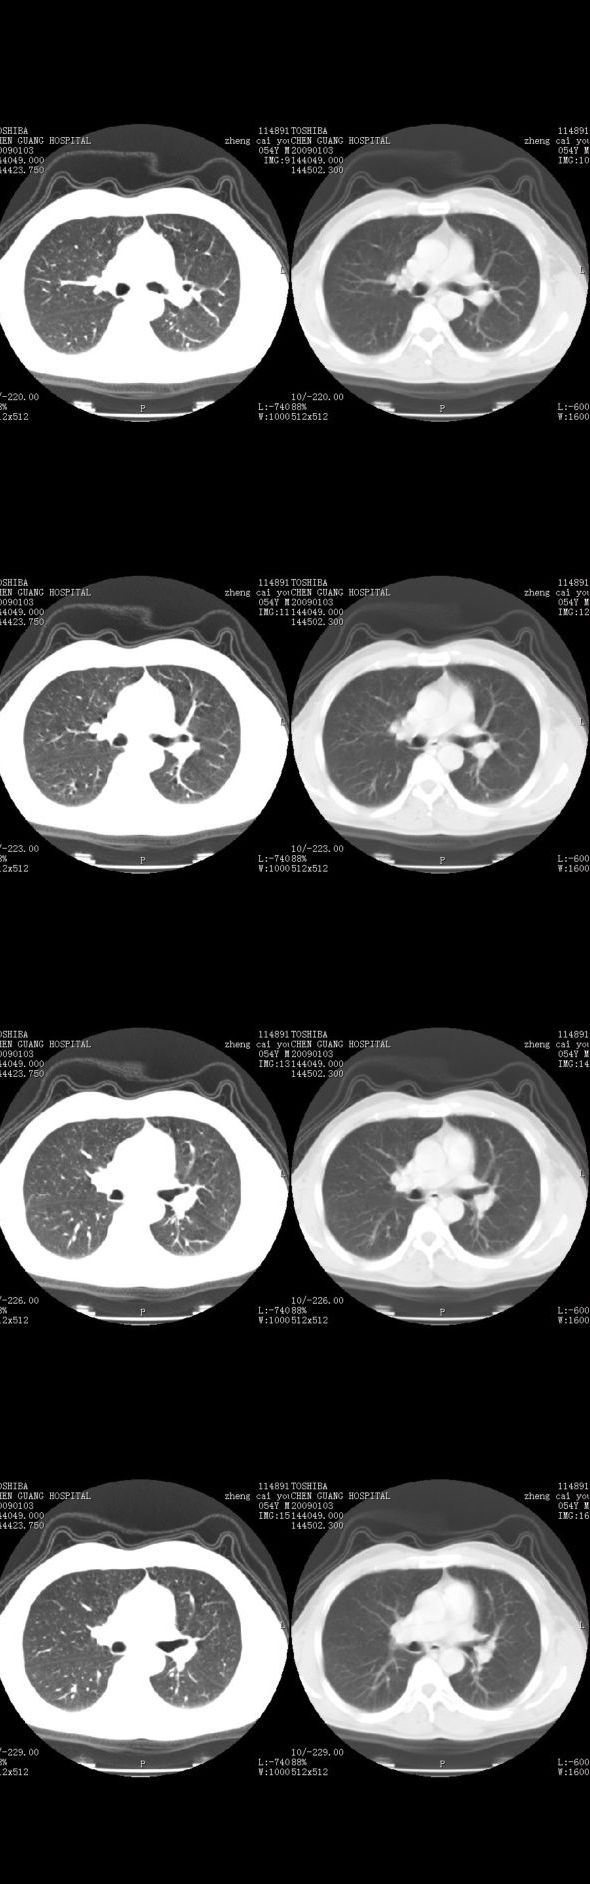

男,54岁,平时有吸烟后咳嗽、咯痰史,因右侧胸部(腋窝下)疼痛来检查平片,见右下肺动脉干起始处处结节,后到同学处做了平扫及增强。请各位老师帮忙看一下,不甚感谢!!!!!

顺序确实有点乱,不过在右肺上叶后段近气管旁仍可见一结节灶,希望楼主小心观察分析。

增强了 但纵隔窗调的看不清  右上叶支气管壁似有增厚 警惕

肺窗薄扫、常规扫描均未见明确病变;右下肺门圆形与肺血管等密度影,考虑为血管变异;应该要纵隔窗才能进一步明辨。

x线表现与ct扫描相吻合。

右肺上叶前后段支气管夹角处可见一结节影,图像资料不全,不好下结论。